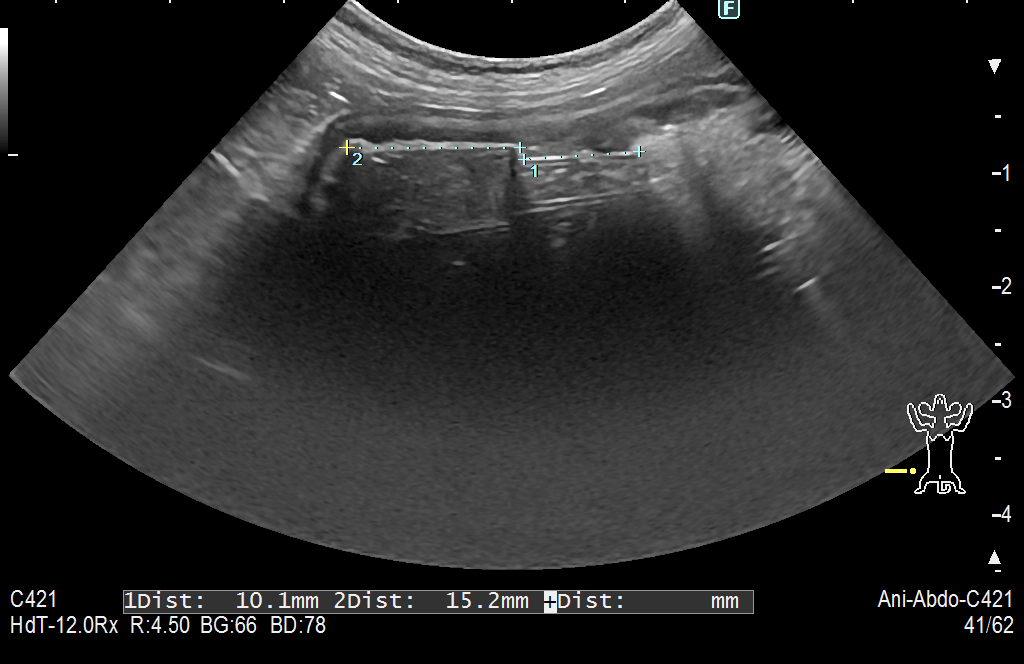

異物はこんな風に見えることがおおいです 2026年02月07日 異物を飲み込んでしまった時にそれがプラスチックやコルクなどの商品だった場合 レントゲンでは映ってはきませんが 超音波では結構映ります 映らないと思っている先生や患者さんも多いのですが 実は こんな風に映っていきます これはキャップです 見えますか?? 結構超音波で映ってくることが多いので試してみる価値はあると思います